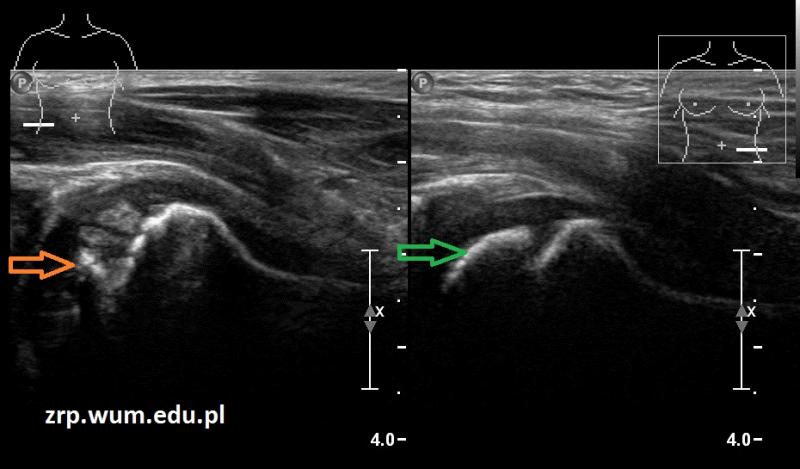

Rozpoznanie: W badaniu USG uwidoczniono spłaszczenie i nerówny zarys nasady głowy kości udowej prawej (pomarańczowa strzałka) - cechy ch. Perthesa. W wywiadzie - chłopiec miał kilka epizodów utykania w ciągu ostatnich kilku miesięcy. Dla porównania - prawidłowa głowa kości udowej lewej (zielona strzałka).